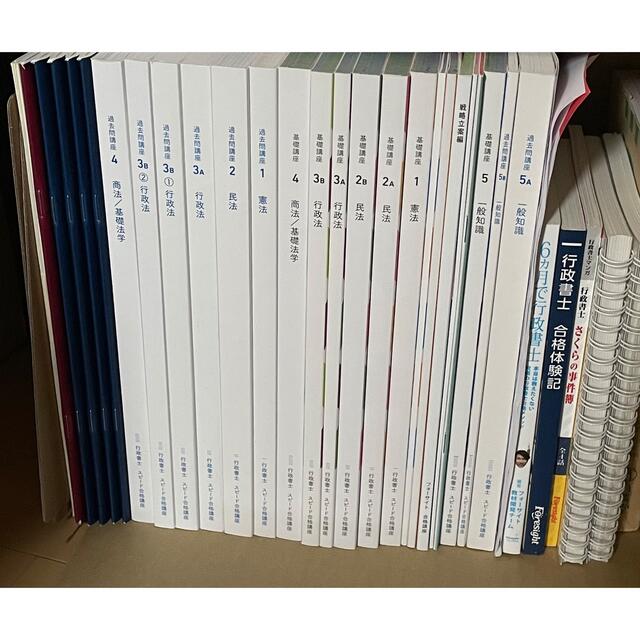

■商品名■

画像から読み解く血管エコー決め手の一枚:読めば納得!検査が変わる!/血管超音波検査の解剖・所見・原理・ピットフォール(ステップアップエコーシリーズ)佐藤洋

■出版社■

メディカ出版

■著者■

佐藤洋

■発行年■

2014/08/04

■ISBN10■

4840449260

■ISBN13■

9784840449267

■コンディションランク■

良い

■コンディション詳細■

書き込みありません。古本のため多少の使用感やスレ・キズ・傷みなどあることもございますが全体的に概ね良好な状態です。水濡れ防止梱包の上、迅速丁寧に発送させていただきます。